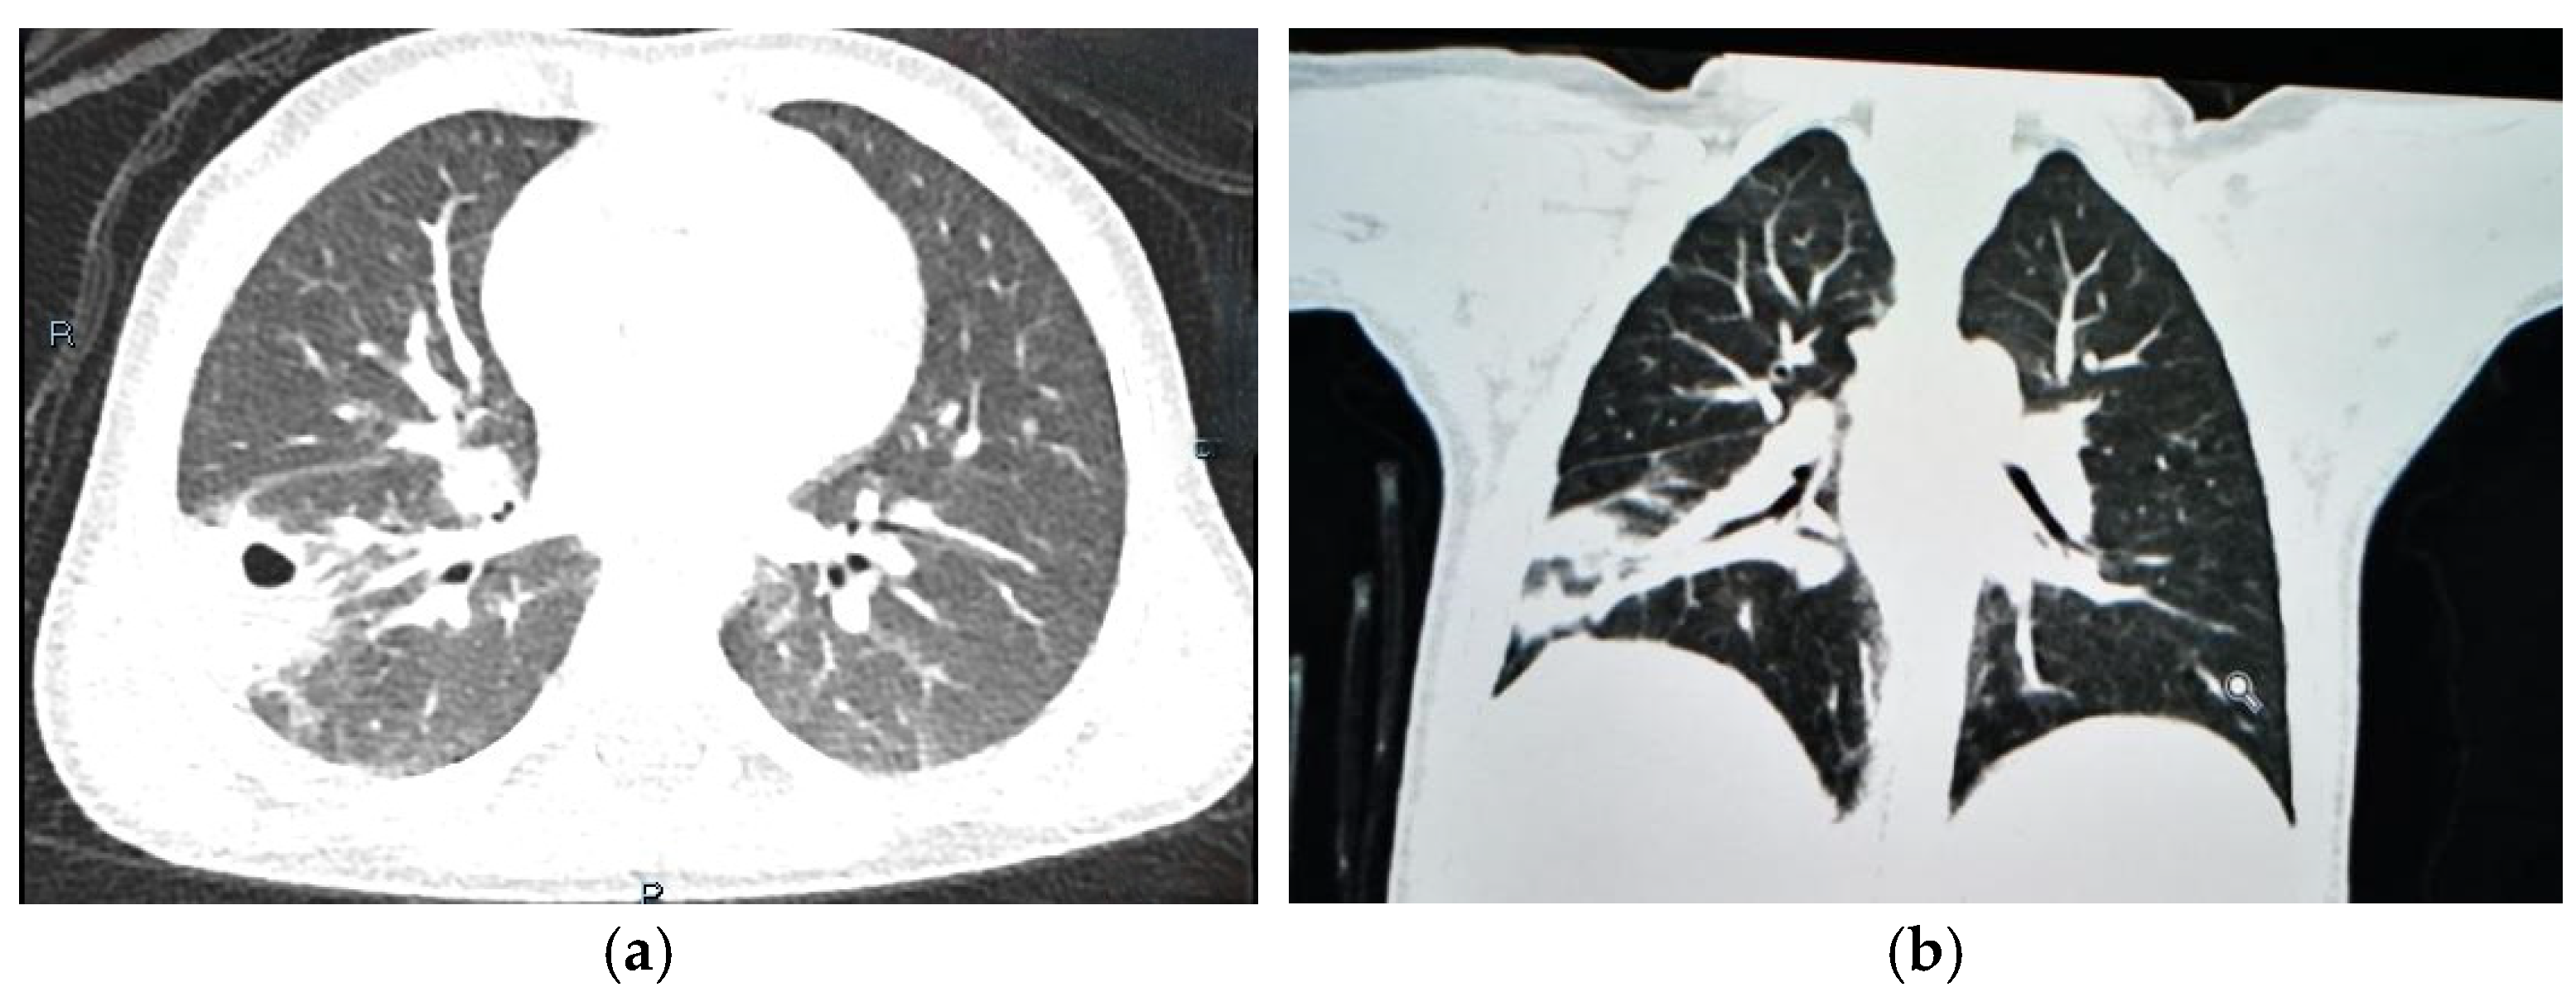

1.9.1. Case 1

1.9.2. Case 2